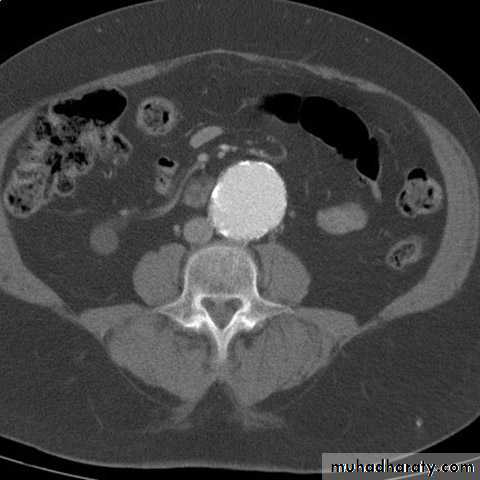

• (AAAs) is true aneurysms commonly involve the infrarenal aorta. aortic diameter >3 cm = AAA.• An AAA of any size can rupture, but those >5 cm are more likely to rupture.

CT Angiogram.

CT Scan